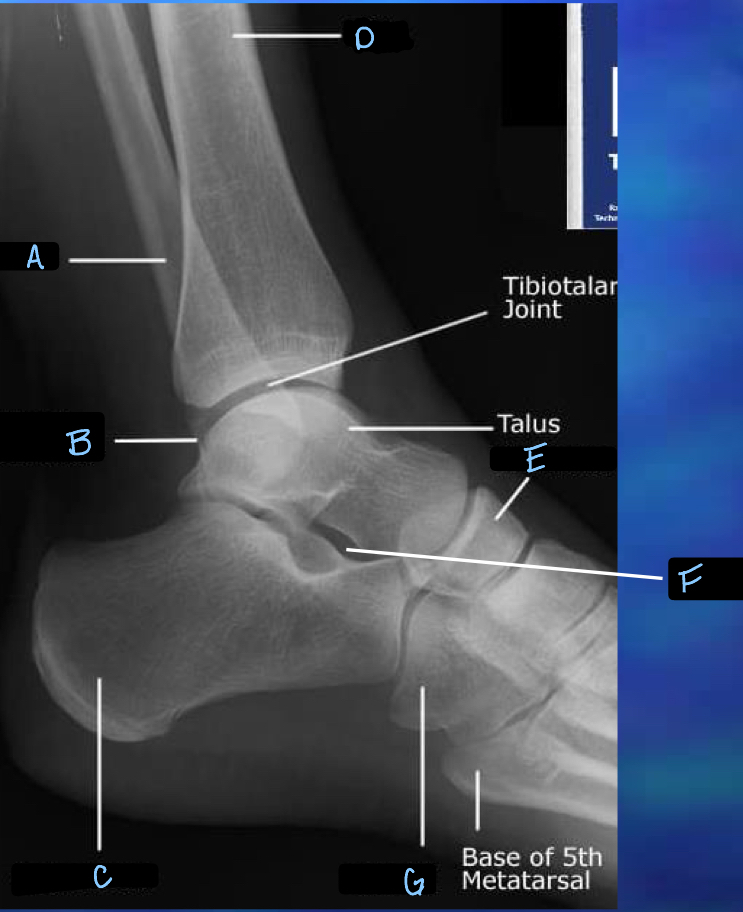

8

What is A?

fibula

9

What is B?

lateral malleolus

10

What is C?

calcaneum

11

What is D?

tibia

12

What is E?

navicular

13

What is F?

sinus tarsi

14

What is G?

cuboid

32

tibotalar joint

33

tarsals

34

metatarsals

35

phalanges

36

sesamoid bones

37

38

What is H?

39

What is I?

40

What is J?